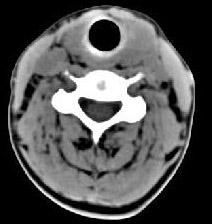

问题 40岁,女性患者,双侧甲状腺肿大,CT扫描如图所示,请选择最佳答案 ( )

选项 A、亚急性甲状腺炎 B、甲状腺瘤 C、甲状腺癌 D、甲状腺炎(桥本) E、弥漫性甲状腺肿

答案 D